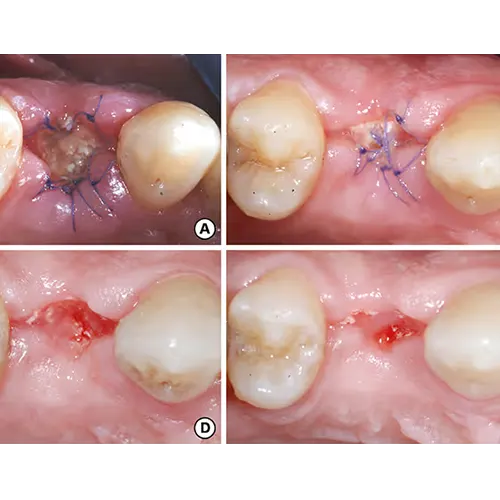

پس از اطمینان از کامل بودن بیحسی، دندانپزشک با استفاده از ابزارهای تخصصی و بسیار ظریف دندانپزشکی، مانند اَلوِاتور (Elevator) و فورسپس (Forceps)، شروع به خارج کردن دندان میکند. هدف اصلی این ابزارها، شل کردن دندان در حفره استخوانی خود و سپس بیرون کشیدن آن است.برای دندانهای ساده: در مواردی که دندان سالم و بدون عارضه است، عمل کشیدن نسبتاً سریع انجام میشود.

برای دندانهای نهفته یا شکسته: در مواقعی که دندان به طور کامل بیرون نیامده (نهفته) یا بخشی از آن شکسته است، ممکن است دندانپزشک نیاز داشته باشد تا یک برش کوچک در لثه ایجاد کند تا دسترسی بهتری به دندان داشته باشد. همچنین، در برخی موارد، برای تسهیل خروج دندان، ممکن است لازم باشد دندان به قطعات کوچکتر تقسیم شود. این تکنیکها، در عین سادگی، به دندانپزشک اجازه میدهند تا با حداقل آسیب به بافتهای اطراف، دندان را خارج کند.

مراقبت پس از کشیدن (Post-Extraction Care):